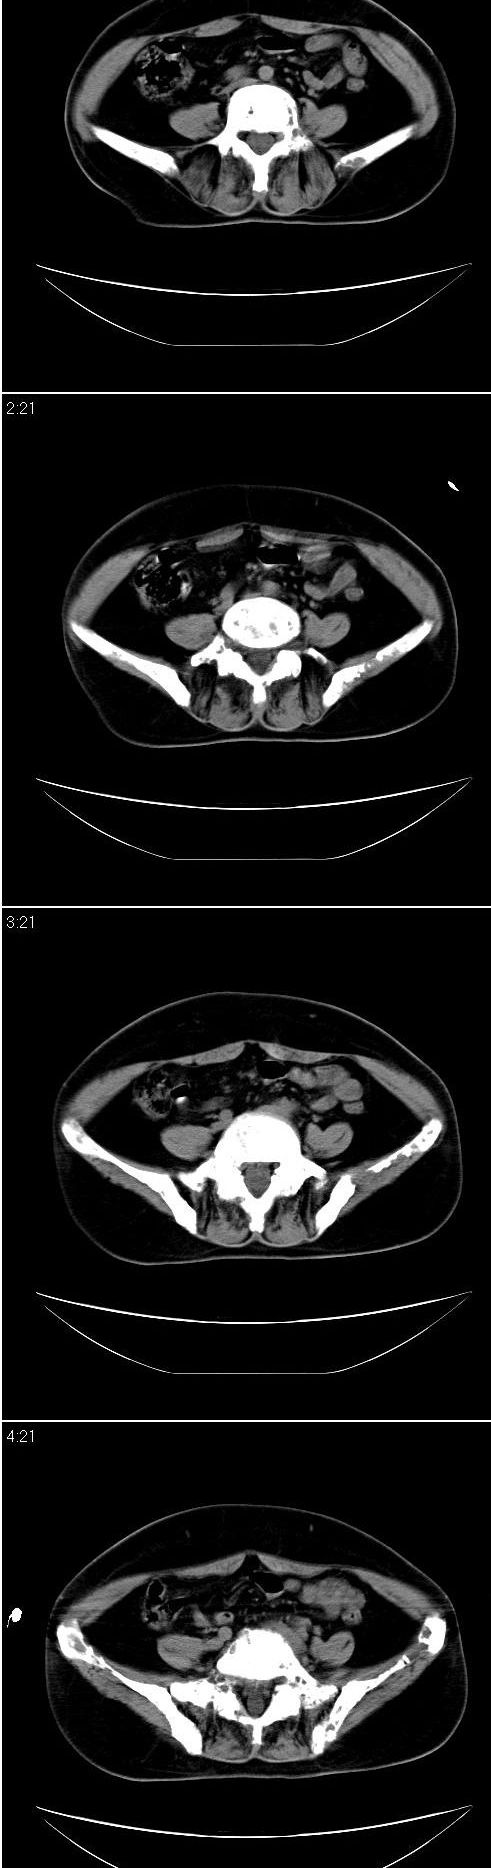

标题: CT13121:女,54岁。乳腺癌术后8年。 [打印本页]

女,54岁。乳腺癌术后8年。现感觉左腿酸困不适,并向下放散。左腿僵硬,不由自主。

典型溶骨型转移瘤。

骨盆及腰椎多发性溶骨性转移瘤.

成骨及融骨转移。

结合病史考虑乳腺癌术后多骨骨转移。

支持 骨转移瘤---混合型以溶骨为主

结合临床考虑多骨多灶性溶、成骨性转移。